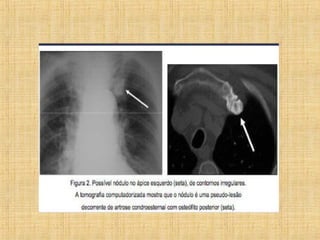

As principais informações do documento são: 1. Discute os padrões de doença pulmonar causados por metástases, incluindo nódulos, espessamento intersticial e obstrução das vias aéreas. 2. A prevalência de metástases pulmonares varia de 30-55% dependendo do tumor primário, e são mais comuns em pacientes acima de 50 anos. 3. Os achados clínicos mais comuns são dispneia, hemoptise e febre, enquanto exames de escarro ou lavado brô